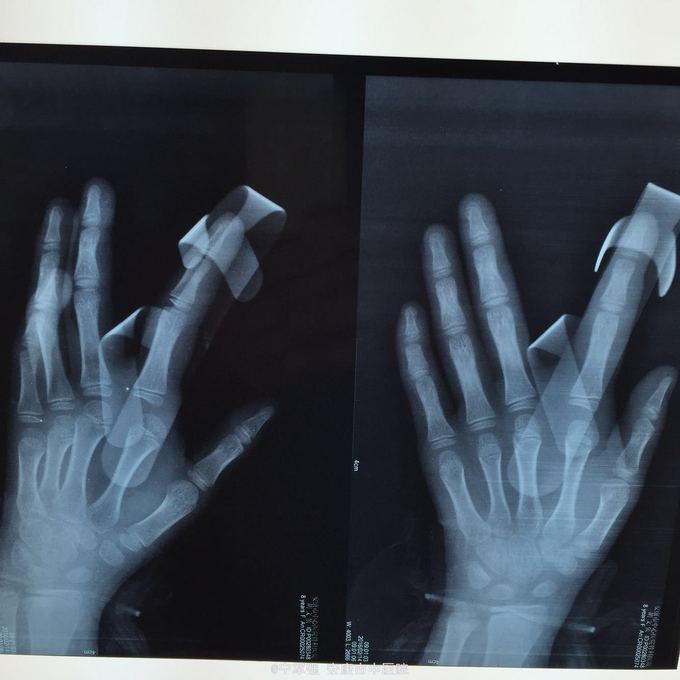

患者8岁,女 扭伤致左手食指肿痛活动受限2小时

患者一般情况良好,左手第二掌指关节处肿胀,弹性固定于伸直位,活动受限,压痛明显,循环尚可

诊断:左手第二掌指关节脱位 处理,予以手法复位失败!考虑关节囊坎顿,阻止复位 予以局麻小切口探查证实,复位脱位,修补关节囊

指骨夹板固定,复查x线显示复位良好 随诊